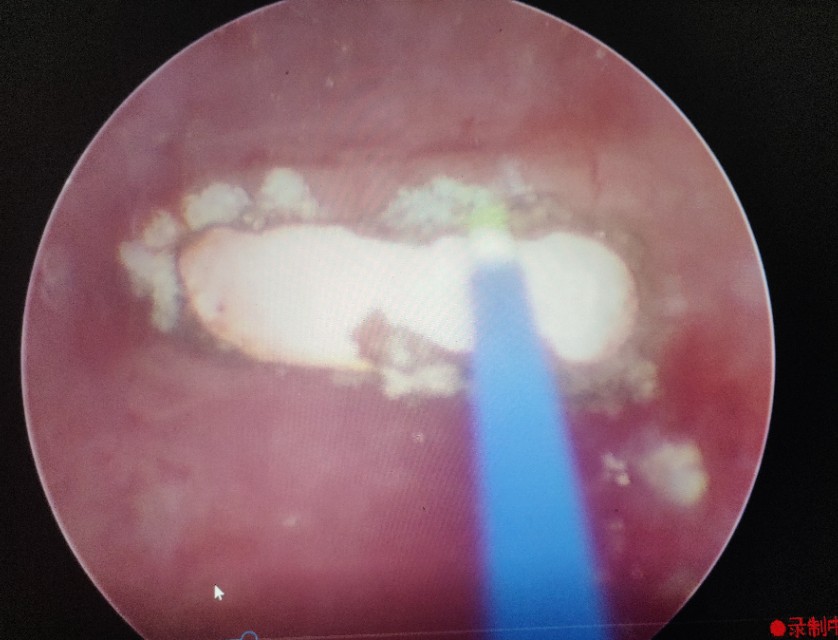

外一科主任靳永池认为此为罕见病例,随即安排主治医师何晓北为患者进行膀胱镜检查,膀胱镜下两枚奇异的结石无所遁形,灰白色,一大一小,固定于膀胱顶部,与膀胱壁间有蓝绿色金属丝相连。妇产科副主任医师李丽芬和主治医师周秀军一致认为,此为“爱母环”移位进入膀胱并形成结石。

在手术室、麻醉科支持下手术开始,何晓北用钬激光一点点的将两枚结石击打成小碎块,随着结石的去除,节育环渐渐露出了真容,粉红色的两个端头丝毫不像能给患者带来剧烈腹痛的样子。何晓北用激光击打节育环的金属丝,靳永池带领的外一科团队紧盯着屏幕,做好了实施第二、三套方案的准备。随着几次亮光闪烁,节育环成功打断,接着从另一侧取出节育环剩余部分,去除碎石屑,手术顺利,成功结束。